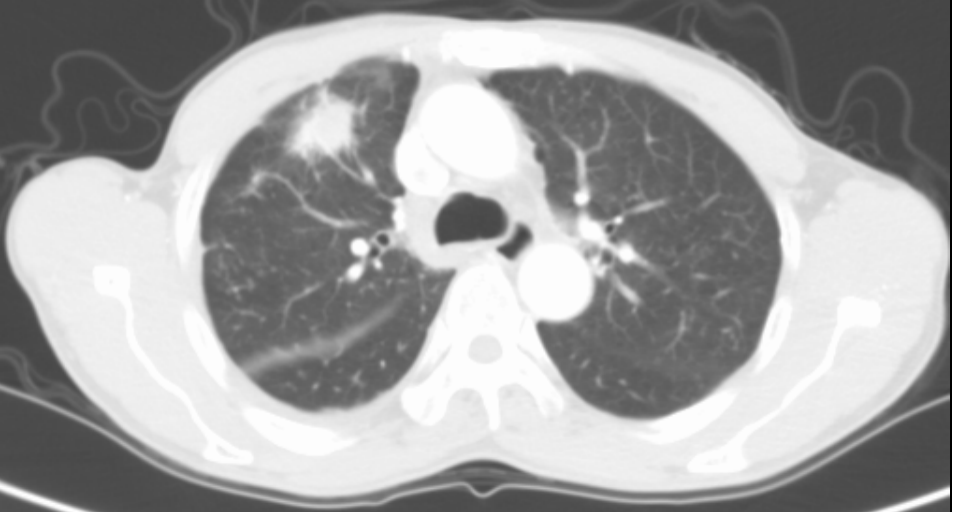

经与患者及家属充分沟通后,呼吸与危重症医学科三区为吴伯安排了肺结节微波消融术。术前已行结节活检,病理结果提示为腺癌。手术过程中,在副院长许承琼指导下,通过CT引导定位,布针顺利平稳,布针结束后,随即展开肺结节微波消融术,手术历时不到2小时顺利结束。